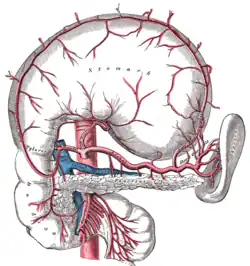

Blutversorgung der Bauchspeicheldrüse

Die Versorgung der Bauchspeicheldrüse erfolgt über drei größere Gefäße: Die obere Bauchspeicheldrüsen-Zwölffingerdarmarterie (Arteria pancreaticoduodenalis superior), die große Bauchspeicheldrüsenarterie (Arteria pancreatica magna) und die untere Bauchspeicheldrüsen-Zwölffingerdarmarterie (Arteria pancreaticoduodenalis inferior) verzweigen sich in weitere kleinere Arterien, die zum Teil miteinander in Verbindung treten (anastomosieren).[5]

Das venöse Blut aus Körper und Schwanz der Bauchspeicheldrüse wird von kleinen Bauchspeicheldrüsenvenen (Venae pancreaticae) über die Milzvene (Vena splenica) in die Pfortader (Vena portae) geleitet. Das Blut aus dem Kopf der Bauchspeicheldrüse gelangt über die Bauchspeicheldrüsen-Zwölffingerdarm-Vene (Vena pancreaticoduodenalis) in die obere Gekrösevene (Vena mesenterica superior) und dann ebenfalls in die Pfortader.[6]